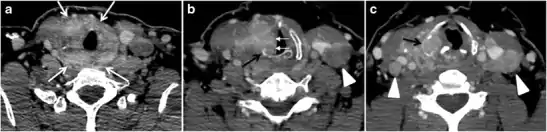

Thyroid lymphoma represents about 5% of thyroid malignancies. Non-Hodgkin's lymphoma is the most common type and can be secondary to generalized lymphoma or a primary tumour. Primary thyroid lymphoma usually pre-exists with Hashimoto's thyroiditis. On CT scans with and without contrast, lymphomas tend to have low attenuation values. Thyroid lymphomas have a variable appearance and mostly manifest as a solitary mass (80%). They may also manifest as multiple nodules (15% to 20%) or as a bulky mass replacing the entire gland with extra-thyroid extension (Figs. 11 and and12).12). The presence of cervical lymphadenopathy supports such a diagnosis. Although it is uncommon, tumour necrosis has been reported.[1]

Goiter

A goiter is an abnormal thyroid gland proliferation that manifests as multi-nodular, uni-nodular, or non-nodular diffuse glandular enlargement. A goiter is formed of solid matrix, colloid cysts, blood products, calcification, and fibrosis, and this heterogeneity may lead to variable appearances on a CT scan (Figs. 13, 1414 and and15)15). The US is more sensitive in evaluating thyroid nodules within a goiter; however, a symptomatic goiter may require surgical treatment with total thyroidectomy, and in this case CT plays an additional role in preoperative evaluation. Specific aspects for examination on a CT scan during the preoperative evaluation for goiter include extension, mass effect, and suspicious features of malignancy.[1]

Malignancy can coexist within the goiter and a CT scan may give a clue if there are abnormal cervical lymph nodes and/or signs of invasion. Retrosternal extension (Fig. 15) could affect the surgical approach, as a lower extent may require a partial or total sternotomy to facilitate complete resection. Therefore, the distance of the retrosternal extent from the sternal notch should be measured on a sagittal image.[1]

The interpreting radiologist should describe the mass effect, detailing its degree and direction of displacement of central structures, including the trachea, oesophagus, larynx, and pharynx. Attention should be directed to the upper extent of the goiter and structures immediately surrounding the thyroid gland, including the neuro-vascular structures, retropharyngeal space, and pre-vertebral space. The reporting radiologist should evaluate the vocal cords for symmetry and signs of vocal cord palsy.[1]

Inflammatory lesions

Inflammatory thyroid disorders include acute infectious thyroiditis, Hashimoto's thyroiditis, Riedel's thyroiditis, and granulomatous thyroiditis (de Quervain's). Hashimoto's thyroiditis is associated with an increased risk of lymphoma and papillary thyroid carcinoma. The CT scan findings of thyroiditis are nonspecific and variable (Figs. 14, 1515 and and16)16). The thyroid gland has a very high iodine concentration, resulting in high CT attenuation (80–100 Hounsfield Units). The presence of thyroiditis can be suggested by a diffusely enlarged and hypo-attenuating (around 45 Hounsfield Units) thyroid gland. This is probably due to follicular cell destruction and reduced thyroid iodine concentration. Marked homogeneous enhancement is typically expected. Therefore, moderate thyroid enhancement in a case of thyroiditis suggests a diffuse inflammatory process. It is essential to clinically correlate this with a thyroid function test and serum autoantibody levels.[1]

Fig. 16. Midline ectopic thyroid with Hashimoto's thyroiditis in a 49-year-old female patient. a Transverse greyscale ultrasound shows a 1.6 × 0.8 cm solid, well-defined, heterogeneous area (white arrow) in the midline, superior to the thyroid gland. It is iso-echogenic to the thyroid gland with no definite connection to the thyroid gland. b Transverse colour Doppler ultrasound shows significant increase in vascularity. c Axial enhanced neck CT scan at the level of thyroid cartilage demonstrates midline infrahyoid hyperdense soft tissue mass (white arrow) embedded within the strap muscle.[1]

Ectopic tissue/gland

During embryogenesis, the bi-lobed thyroid migrates inferiorly from the foramen cecum of the tongue to the lower neck. Initially, the thyroid primordium passes anterior to the primordial hyoid bone, before it loops posteriorly and inferiorly to the hyoid bone. Then it continues its descent into the infra-hyoid portion of the neck, anterior to the trachea, thyroid cartilage, and thyroid membrane. Any thyroid residual along the descent course may lead to the development of ectopic thyroid glands. Thyroid carcinomas, thyroiditis, and goiter may develop within any ectopic thyroid tissue.[1]

Thyroid scanning with technetium-99 m (Tc99m) plays an important role in detecting orthotopic and ectopic thyroid tissue. Both CT scans and US can help detect ectopic tissue when a lesion demonstrates imaging and enhancement characteristics of thyroid tissue. The absence of normally sited thyroid gland in US and CT scans also supports the diagnosis. In addition, US can guide FNA for cytological confirmation of a thyroid lesion. Ectopic thyroid tissue appears as a well-circumscribed, homogeneous, highly attenuating mass relative to adjacent muscles. Normally, it enhances avidly following the administration of iodinated contrast.[1]

Ectopic thyroid tissue may be detected in the tongue near the foramen cecum (90%) and along the midline between the thyroid isthmus and posterior tongue, lateral neck, mediastinum, and oral cavity. The most frequent location is the base of the tongue (Figs. 16, 1717 and and18).18). In 70% of cases, the ectopic thyroid is the only functional thyroid tissue present in the body (Fig. 18).[1]

Ectopic thyroid tissue lateral to the orthotopic midline location is rare. The exact anatomical definition of this rare entity is debated in the literature. To avoid confusion, some authors define a lateral neck ectopic thyroid as any thyroid tissue superficial to the strap muscles with no midline continuity. The majority of lateral thyroid ectopia cases have been reported as lesions closely related to the strap muscles. There are few reported cases of ectopic lateral thyroid tissue in the submandibular region, jugulodigastric region, or within the parotid gland substance (Fig. 17).[1]